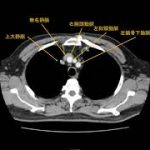

大血管(大動脈、大静脈、肺動脈、肺静脈)気管支、食道の位置関係を確認しましょう。 終了後は、受講登録のアンケートと小テストをお願い .....